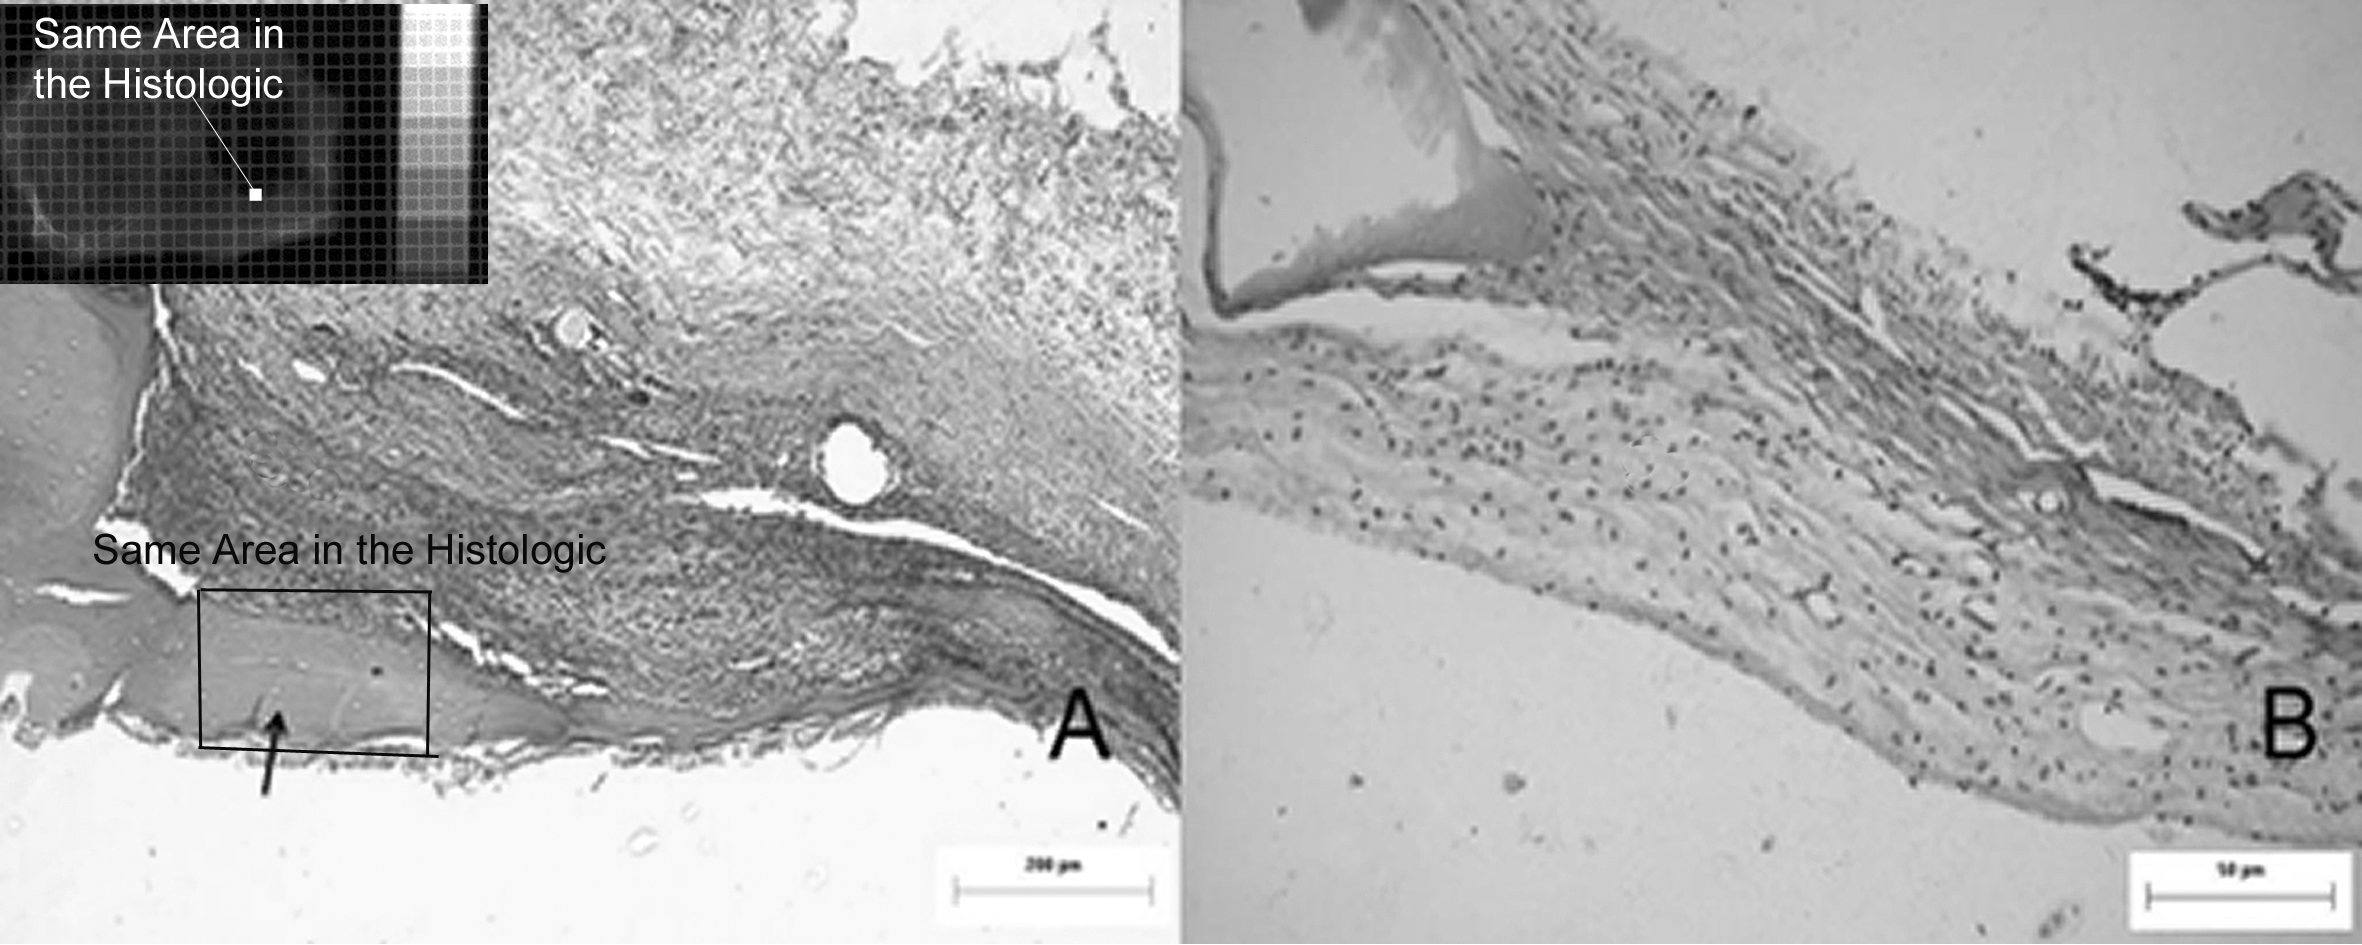

The aim of this study was to evaluate the optical density of the zirconia granules used as a graft in a rat calvarium model. Forty animals (Rattus Novergicus, albinus, Wistar) were divided into control and experimental groups and submitted to bone detects in the cranial cap using a trephine type burr 6 mmin diameter. The control group had the defect filled with blood coagulum, and the experimental group was filled with zirconia granules of 300 to 850 µm. The animals were sacrificed at intervals of 7, 14, 30, and 60 days. Digital images were obtained from the bone defect region, and optical density of the zirconia granules was measured using the Image Tool® 3.0. software (UTHSCSA,San Antonio, EUA). The histological analysis of the specimens was also evaluated. The values obtained were analyzed by statistical methods: Analysis of Variance, Welch’s Anova, and F Test. It was verified that the mean optical density of the bone repair process differs in all analyzed regions, irrespective of time (p < 0.0001). In the region with the zirconia graft, the mean density was always higher than the other regions analyzed, and the control group showed the same behavior of the experimental groups, but for the region with zirconia graft, the average density is always greater.